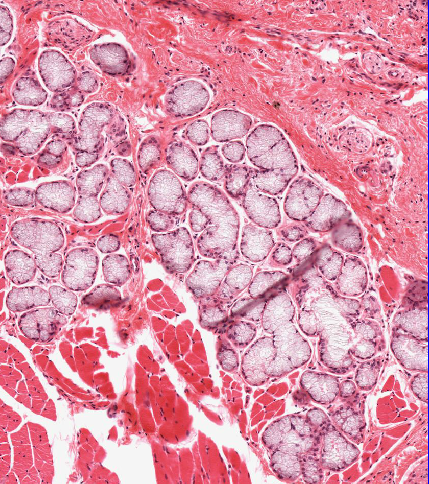

This has been taken from the tongue. What is?

Mucus secreting salivary gland